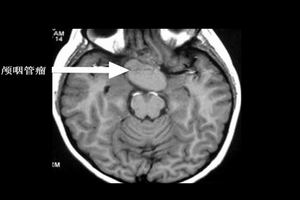

顱咽管瘤(craniopharyngioma)又稱拉克(Rathke)囊瘤、垂體管瘤(tumorofhyphophysisduct)、垂體造釉細胞瘤(Pituitaryadamantinoma)、鞍上囊腫(suprasellarcyst)等。有人認為是胚胎期顱咽囊殘留上皮發生的腫瘤,不屬於內分泌腫瘤。該瘤約占顱內腫瘤的1%~5%,多見於20歲以前的青少年,大多數腫瘤位於蝶鞍上,也可位於蝶鞍外沿顱咽管的各部位。肉眼觀:腫瘤有假包膜,與周圍組織粘連,呈浸潤性生長,其生物學行為屬低度惡性腫瘤。腫瘤大小不一,一般直徑約3cm-5cm,切面可為實性或單、多囊性。囊內可含暗褐色液體;光鏡下:瘤組織似造釉細胞瘤。瘤細胞排列成巢,細胞巢周邊有1-2層柱狀細胞,稍內為棘細胞,向中心逐漸變成星狀細胞或壞死、液化形成囊,可有膽固醇結晶和鈣鹽沉積,囊壁內由鱗狀上皮構成。

顱咽管瘤是由外胚葉形成的顱咽管殘餘的上皮細胞發展起來的一種常見的胚胎殘餘組織腫瘤,為顱內最常見的先天性腫瘤,好發於兒童,成年人較少見,好發於鞍上。其主要臨床特點有下丘腦-垂體功能紊亂、顱內壓增高、視力及視野障礙,尿崩症以及神經和精神症狀,CT檢查可明確診斷。治療主要為手術切除腫瘤。

2.CT掃描顱腦CT掃描顯示為鞍區腫瘤改變,非增強掃描者實質性腫瘤表現為高密度或等密度影像,鈣化斑為高密度,囊性者因瘤內含膽固醇而呈低密度像,CT值為-40~10Hu,囊壁為等密度。病變邊界清楚,呈圓形、卵圓形或分葉狀,兩側側腦室司擴大。強化掃描時約2/3的病例可有不同程度的增強,CT值增加12~14Hu,囊性顱咽管瘤呈環狀強化或多環狀強化而中心低密度區無強化,少數顱咽管瘤不強化。一般具有鈣化、囊腔及強化後增強三項表現的鞍區腫瘤。